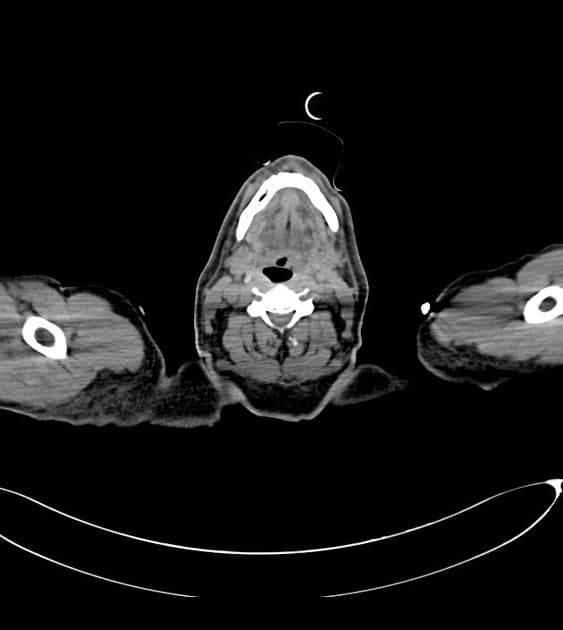

- Thấy vạt bóc tách (flap) trong động mạch chủ (aorta), xuất phát ở đoạn động mạch chủ lên (ascending aorta) ngay phía dưới gốc động mạch chủ (aortic root), xoắn dọc theo toàn bộ động mạch chủ (aorta), tạo thành buồng giả (false lumen) lớn nằm chủ yếu phía sau và chèn ép buồng thật (true lumen), buồng thật có hình bầu dục trên mặt cắt ngang.

- Toàn bộ động mạch chủ (aorta) giãn, đường kính lớn nhất tại đoạn động mạch chủ xuống ngực (descending thoracic aorta) đo được 5,1 cm.

- Buồng giả (false lumen) có hiện tượng huyết khối thành mạch (mural thrombus) một phần, không đồng đều, dày nhất ở đoạn động mạch chủ xuống ngực (descending thoracic aorta), làm giảm đường kính lòng mạch khoảng 50%.

Trường hợp này cho thấy hình ảnh bóc tách động mạch chủ (aortic dissection) loại Stanford A / DeBakey I.